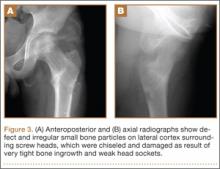

A 10-year-old boy was brought to our emergency department with the chief complaint of left hip pain after a car accident. Anteroposterior and axial lateral radiographs showed a displaced cervicotrochanteric femoral neck fracture (Figures 1A, 1B). The patient was admitted to the hospital and underwent closed reduction and internal fixation with two 3.5-mm cannulated titanium screws within 12 hours of arrival. The screws did not cross the physis to avoid iatrogenic injury of the capital femoral epiphysis (Figures 2A, 2B). The entry point was located at the lower level of the lesser trochanter. The lateral cortex was penetrated only once by the guide wire for the placement of each screw.